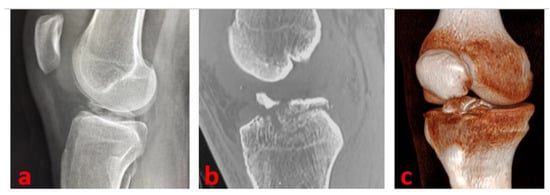

Under arthroscopic and fluoroscopic visualization, we completely extend the knee to confirm the effectiveness of reduction and stability. The Kirschner wires are externally cut (by maintaining a 2–3 cm straight external portion—essential for the subsequent removal) and curved (Figure 4).

Figure 4.

Fluoroscopic control of fracture reduction and osteosynthesis devices positioning of the left knee of a 16-year-old female patient with the knee flexed to 90° (a) and the knee completely extended (b).

At this stage, the tourniquet is let down, the hemostasis performed, and the arthroscopic portals sutured. A compressive bandage and a long-leg cast at 30° of knee flexion (with the K wires anchored to the cast) are applied.